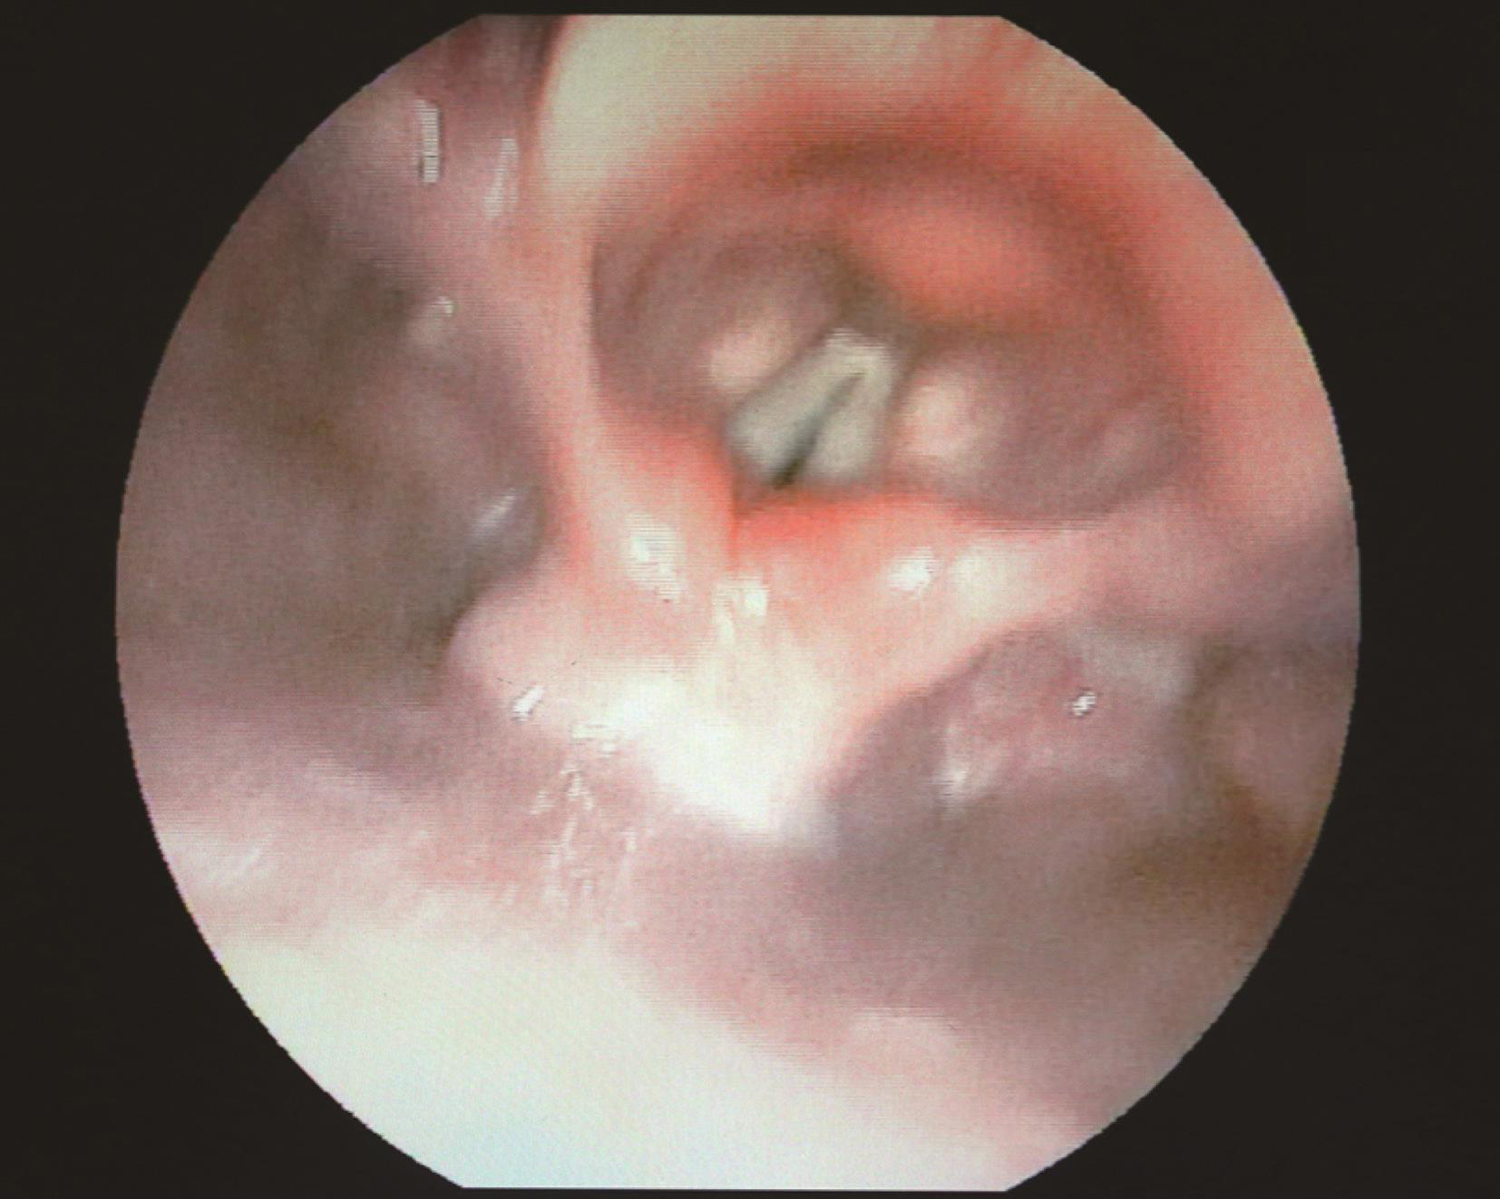

3.2017年8月10日电子喉镜

右侧声带固定于旁正中位,闭合时有裂隙(图5,图6)。

图5 喉镜示右侧声带固定于旁正中位

图6 喉镜示声带闭合时裂隙